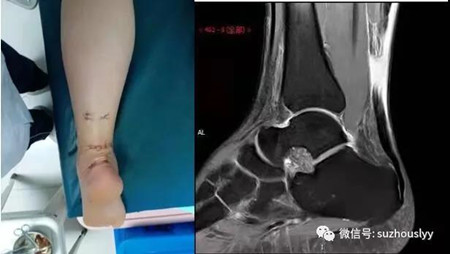

患者为46岁的男性,因打篮球过程中左脚不慎扭伤,导致跟腱断裂,被送到我院普外三科就诊,值班医生接诊后上报科主任杨峰进行会诊检查,经检查与MRI核磁影像结果相符,确诊左脚跟腱完全断裂,需手术治疗。杨耀坤医生在主任杨峰的指导经过近40分钟采用改良微创术手术非常成功,术后效果患者非常满意。

杨主任介绍:该手术方式结合了Lindholm手术方式Ma-Griffith手术方式的优点,通过平行跟腱横断面做一长约3cm的横行切口,远近两端采用盲穿的方式将固定肌腱线从跟腱的远近两端向肌腱断端穿出,然后打结固定,再用肌腱缝合线加固缝合修复肌腱的断端,完美解决了跟腱断端的暴露不完全及盲目缝合的弊端,此项手术方式适用各种急性跟腱断裂,以最小的创伤,实现最好的预后。